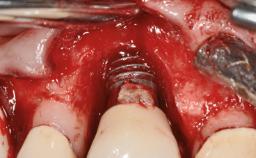

This case describes the ongoing management of a 64-year-old healthy, non-smoking female patient with erosive oral lichen planus (OLP) affecting the gingivae and the buccal and lingual mucosa. The peri-implant mucosa was also affected subsequent to implant placement. The patient had osseointegrated implants (four in the maxilla, four in the mandible) placed following extraction of hopeless teeth and a healing period. The patient had a history of OLP prior to implant placement and had been referred to an oral-medicine specialist for definitive diagnosis and treatment. She exhibited generalized oral mucosal involvement. Following a clinical assessment, biopsy, and blood tests, she was treated with topical corticosteroids. Systemic prednisolone was reserved for severe flare-ups. Amphotericin lozenges were used in combination with corticosteroid treatment to prevent the development of oral candidiasis.

# of Implants 8